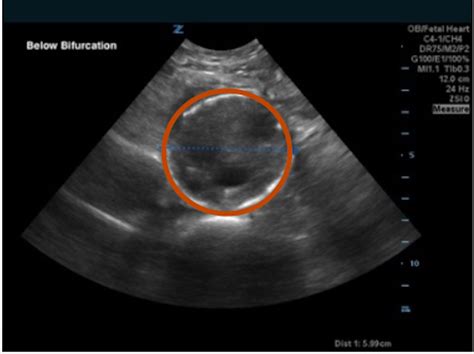

• Ultrasound: This non-invasive test uses sound waves to create images of the iliac arteries and detect any abnormalities.

Iliac Artery Aneurysm, Ultrasound 2 Annotated. JETem 2020 - JETem